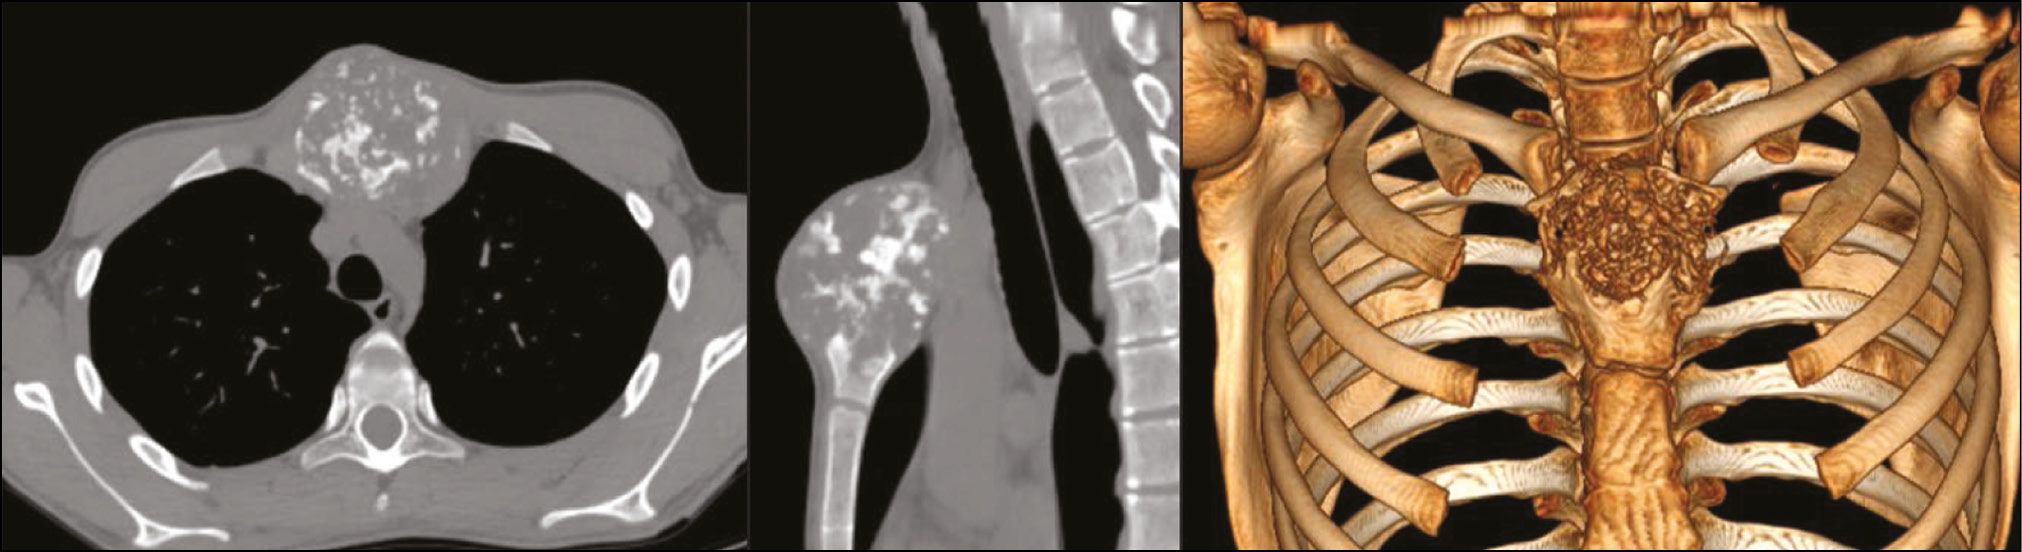

Учитывая локализацию поражения и необходимость тотального удаления рукоятки грудины, необходимый объём резекции существенно снижает каркасность грудной клетки и опороспособность грудино-ключичного сочленения, вторично влияющего на функцию плечевого пояса. Предложенные различными авторами решения этой проблемы в настоящий момент представлены применением стандартных пластин, фиксирующих грудную клетку, или узким использованием аддитивных технологий. В предложенных имплантах замещение опухолевого дефекта выходило на 2-й план в связи со злокачественным новообразованием. Для решения этой клинической задачи по данным DICOM-архива (Digital Imaging and Communications in Medicine — медицинский отраслевой стандарт создания, хранения, передачи и визуализации цифровых медицинских изображений и документов обследованных пациентов) КТ-исследования пациента выполнена реконструкция костной анатомии грудной клетки с опухолью. По итогам создания 3D-модели проведена реконструкция объёма резекции рукоятки грудины для предоперационного планирования импланта (рис. 3).

Рис. 3. Моделирование хирургического вмешательства по данным КТ-исследования пациента Г.

В качестве предоперационной подготовки дополнительно выполнена КТ с контрастированием (рис. 5). Отмечено интимное прилегание к внутренней грудной артерии слева и справа и аорте. Учитывая запланированный объём вмешательства и возможные интраоперационные риски, в операционной бригаде участвовали травматолог-ортопед, онколог, торакальный и сосудистый хирург.

Рис. 5. КТ-артериография с контрастированием аорты и внутренней грудной артерии пациента Г.